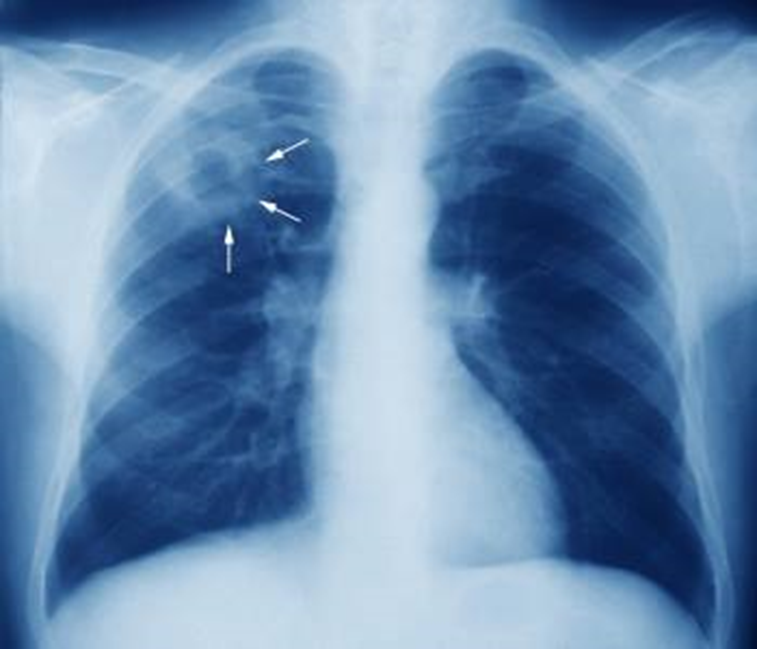

TB CXR looks like what?

Apical cavitation with calcification and hilar lymphadenopathy